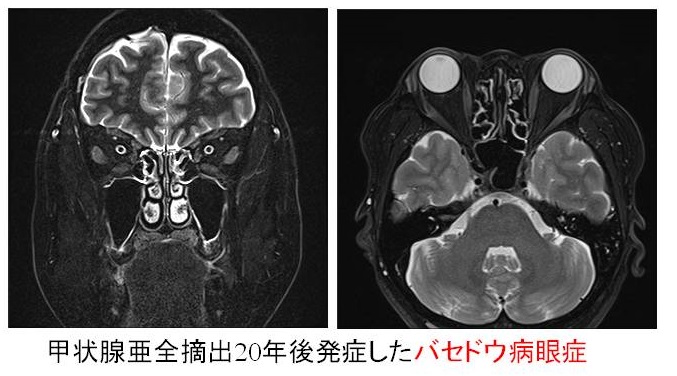

同じく、甲状腺亜全摘出20年後発症した遅延型バセドウ病眼症もありました。